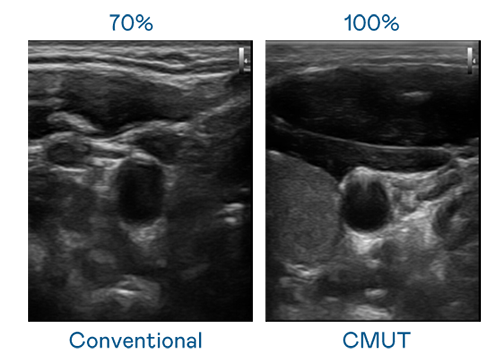

CMUT 技術是一種用電容式微機電元件來產生超音波訊號的技術。與傳統 PZT 壓電式技術相比,CMUT 頻寬增加 30%,更寬頻的超音波訊號讓影像解析度大幅提升,是實現高影像品質醫療超音波掃描、促進精準醫療發展的關鍵技術。

超音波影像的解析度高低,首先取決於探頭能發出的訊號頻寬。至尊国际 CMUT 可提供高清晰的超音波訊號,提供高頻寬、高靈敏度、影像紋理細節更高的超音波影像,協助醫護人員縮短影像判讀時間及利用精準的醫療影像進行診斷。